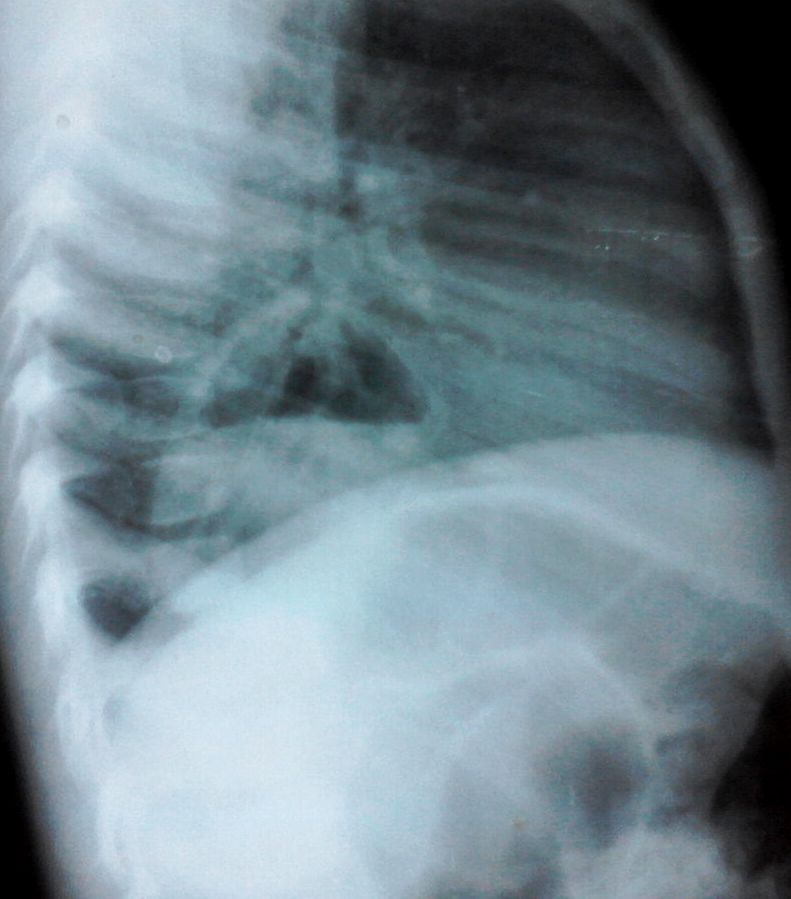

Девочка 4-х лет, жалобы на длительный кашель (оеоло 1-го месяца). В поликлинике выполнена рентгенография органов грудной клетки, выявлены изменения (какие - пока не скажу). Госпитализирована. Направлена на УЗИ сердца. При УЗИ - в самом сердце - патологии не выявлено, но позади него к правому предсердию прилежит полостное образование с акустически неоднородным содержимым.

KapustinSV писал(а):Имхо диафрагмальная грыжа.